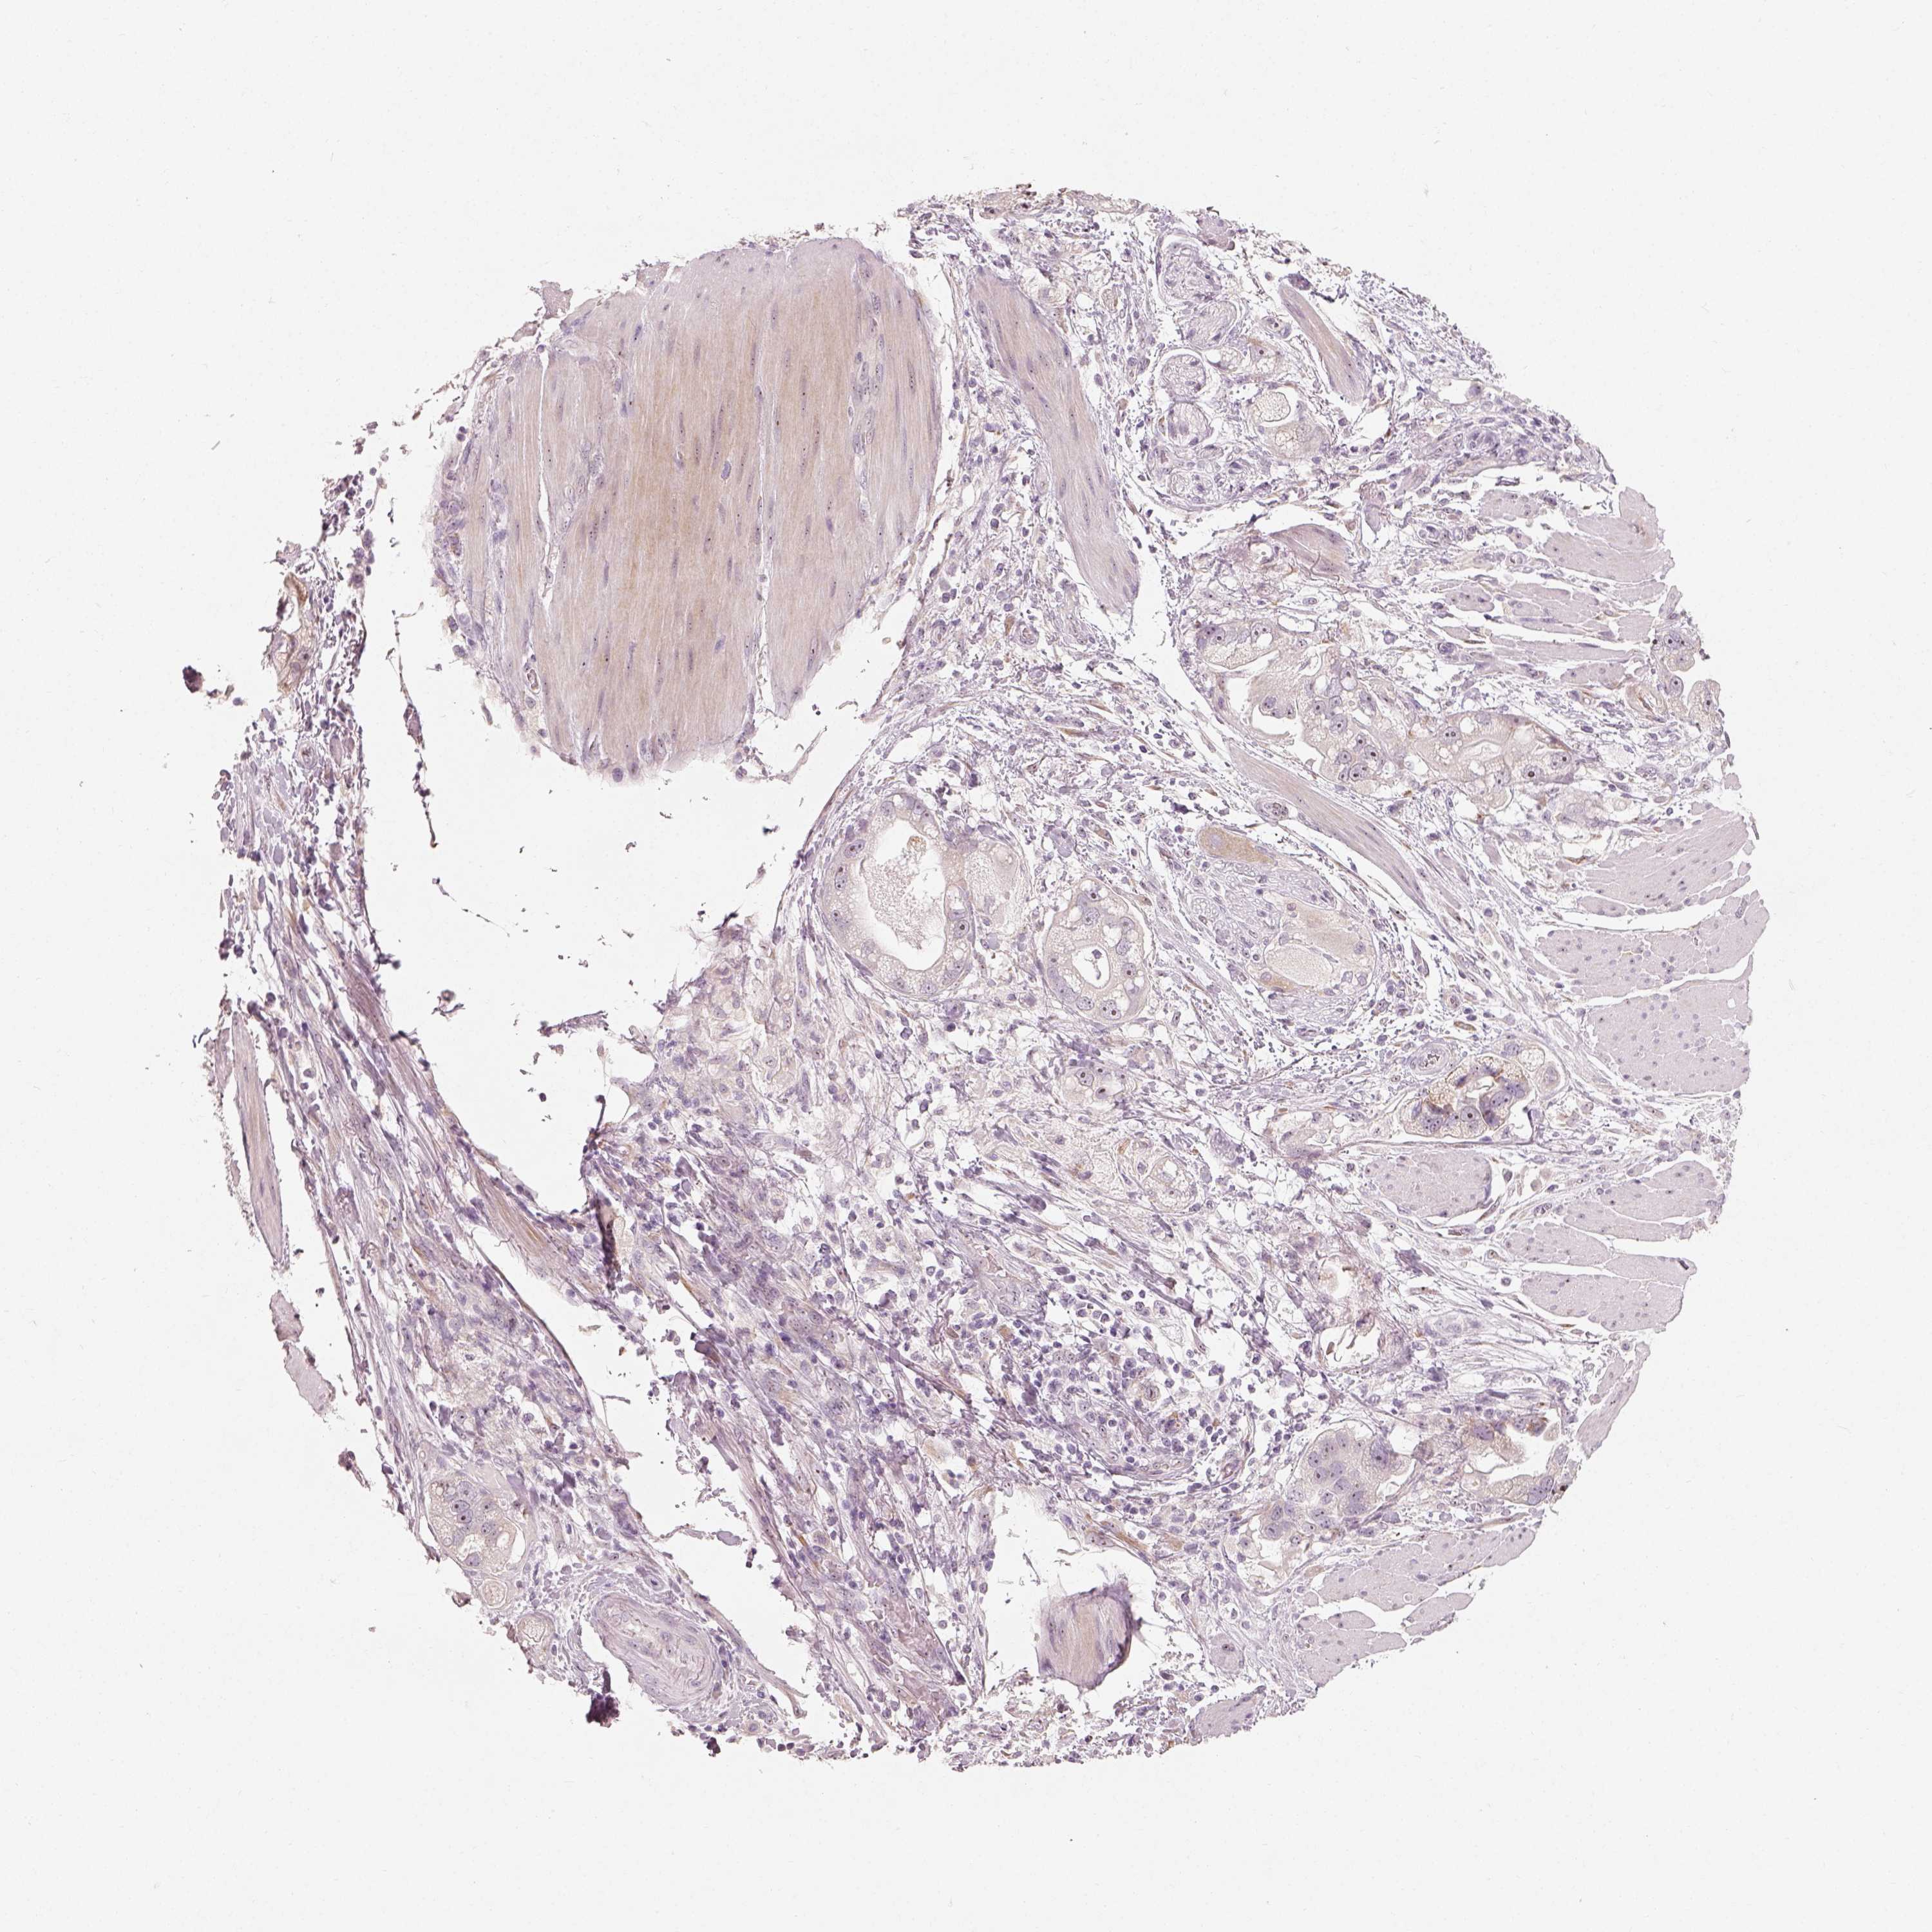

STOMACH CANCER - Protein expressioni

A mouse-over function shows sample information and annotation data. Click on an image to view it in a full screen mode. Samples can be filtered based on level of antibody staining by selecting one or several of the following categories: high, medium, low and not detected. The assay and annotation is described here.

Antibody stainingi

Antibody staining in the annotated cell types in the current human tissue is reported as not detected, low, medium, or high, based on conventional immunohistochemistry profiling in selected tissues. This score is based on the combination of the staining intensity and fraction of stained cells.

Each image is clickable and will lead to virtual microscopy that enables deeper exploration of all samples and also displays staining intensity scores, fraction scores and subcellular localization as well as patient and tissue information for each sample.

Antibody HPA036187

Antibody HPA064546

Staining

High

Medium

Low

Not detected

Intensity

Strong

Moderate

Weak

Negative

Quantity

>75%

75%-25%

<25%

None

Location

Nuclear

Cytoplasmic/membranous

Cytoplasmic/membranous,nuclear

Adenocarcinoma, NOS